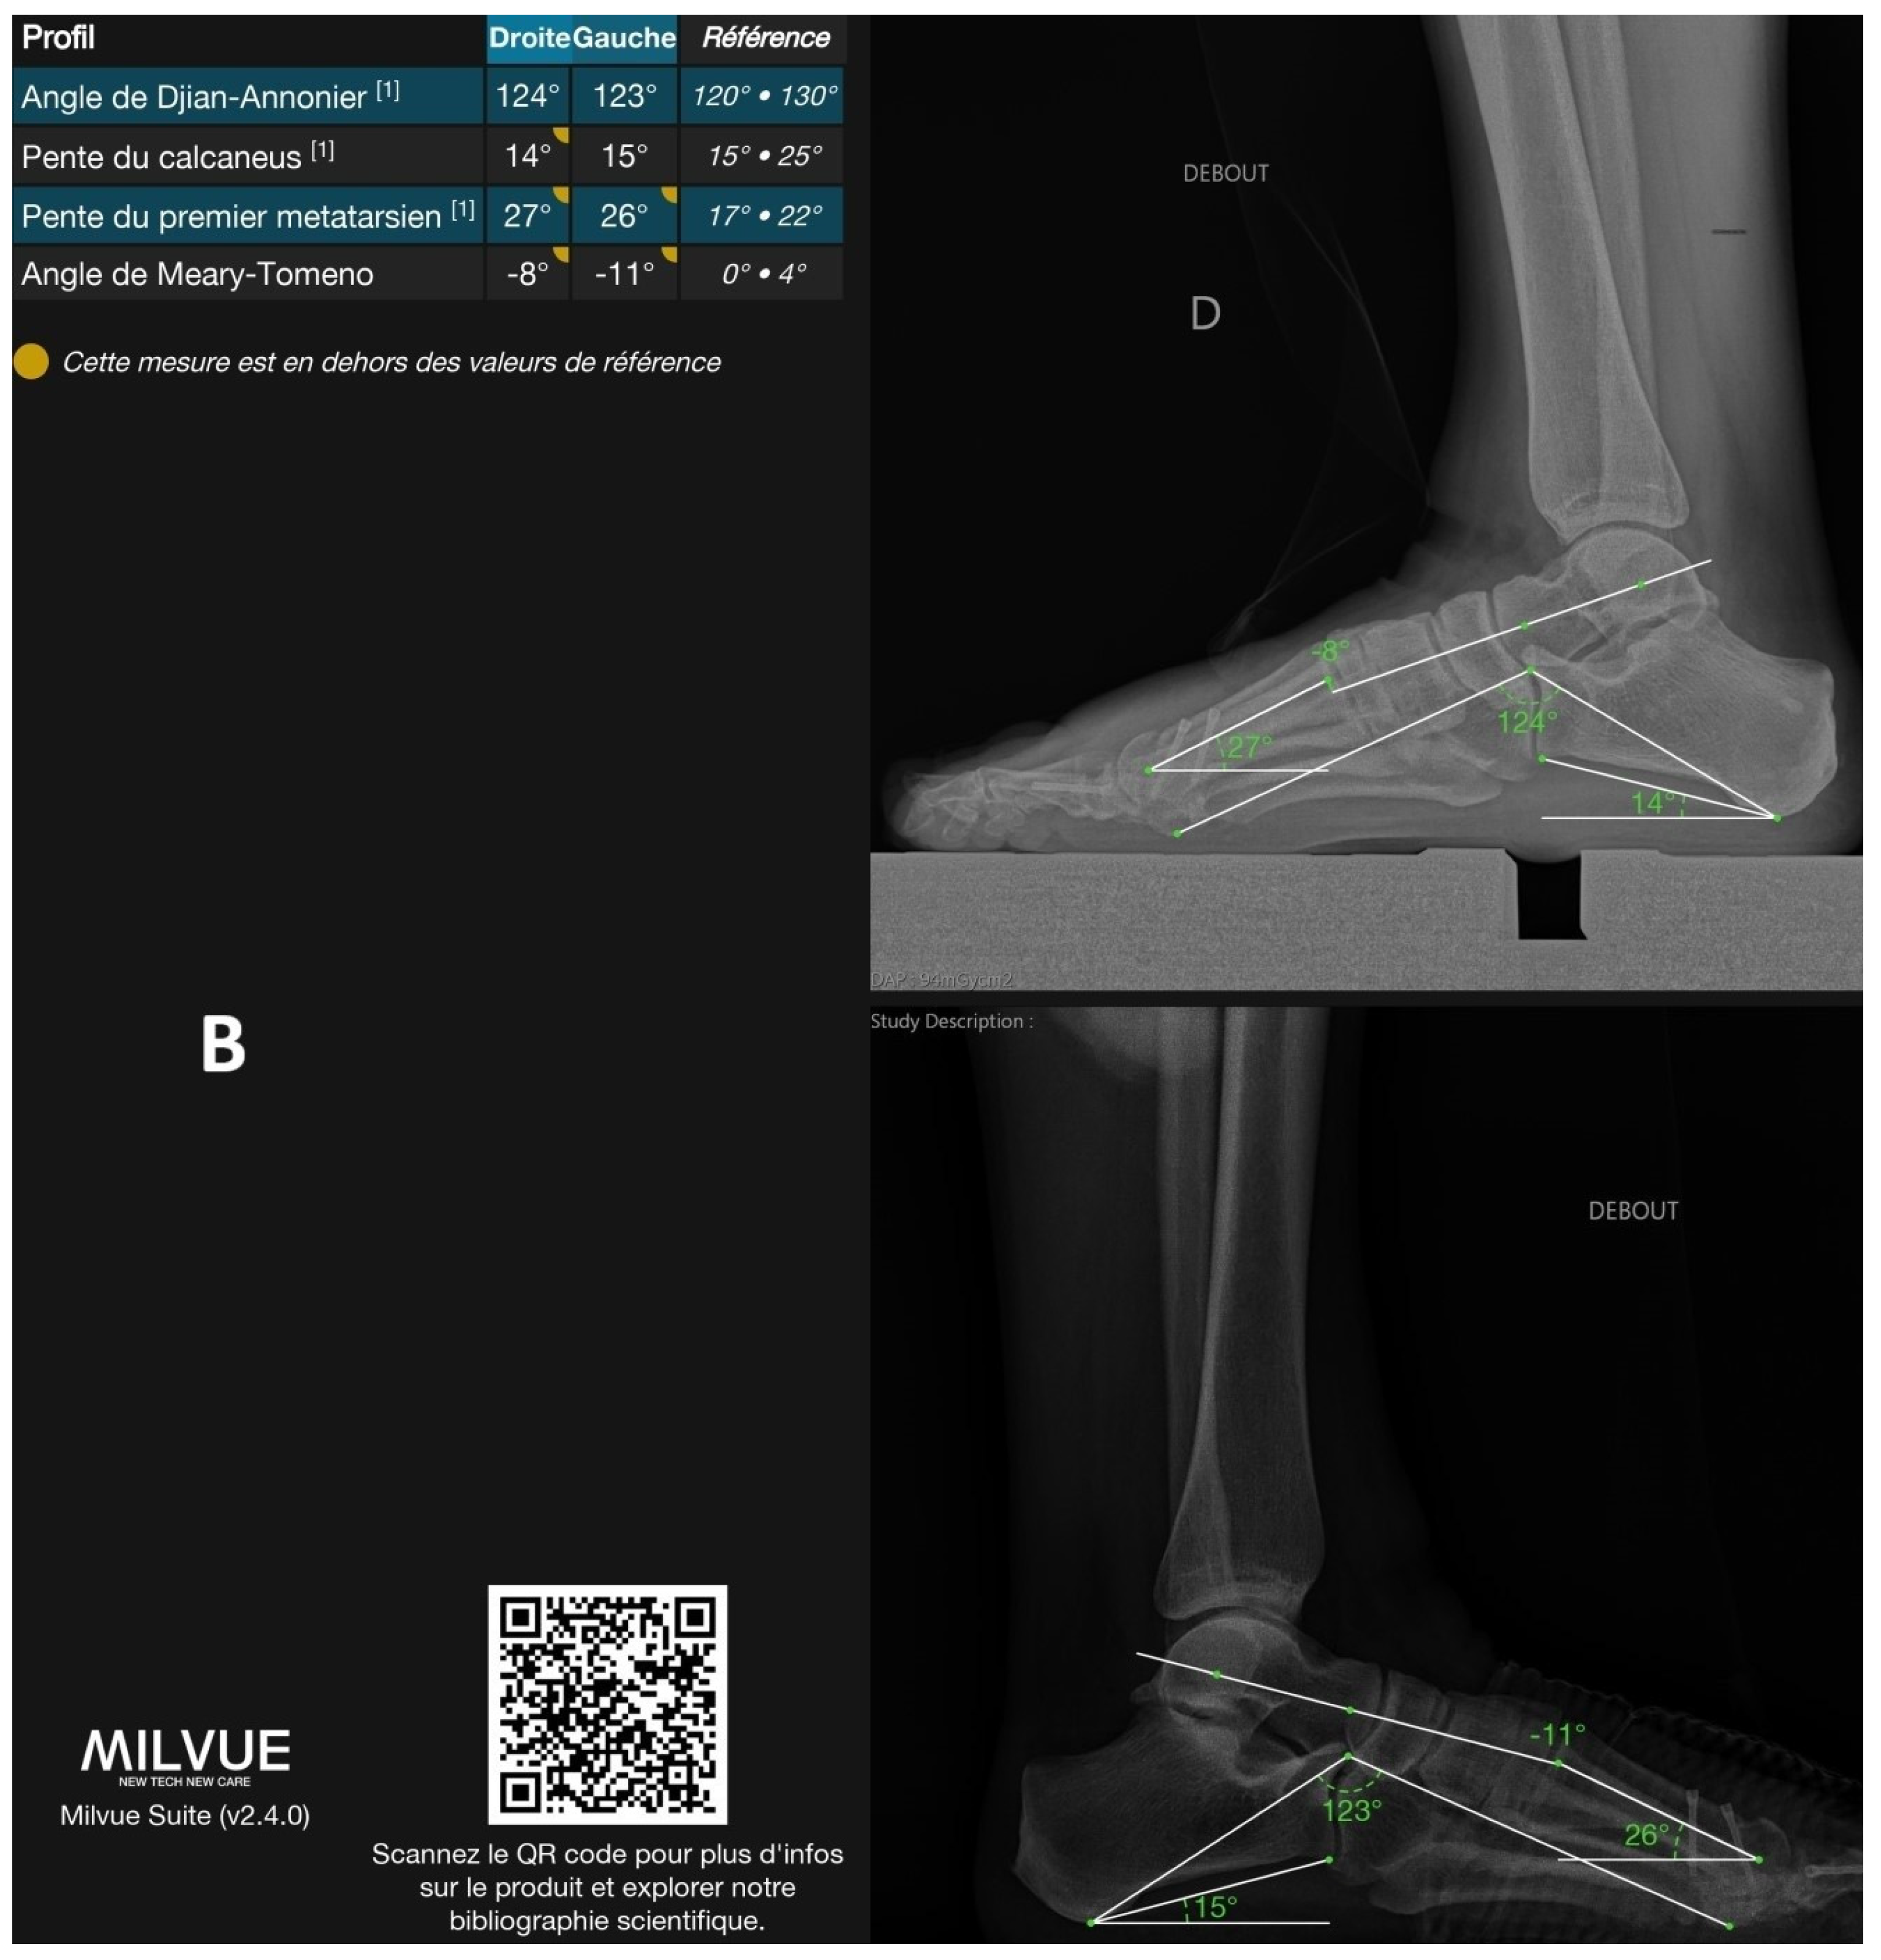

Figure 1 shows an example of a radiograph annotated by the deep learning model, illustrating all automatically detected angles.

Figure 1.

Example of a radiograph analyzed by the deep learning model with all annotated angles. (A): Frontal view. (B): Lateral view. The software output includes a prompt to scan the QR code for more information about the product and to explore related scientific publications, directing to the following URL: https://product.milvue.com/fr/?content=cD1jZSZ2PXYyLjQuMA%3D%3D (accessed on 5 June 2025).